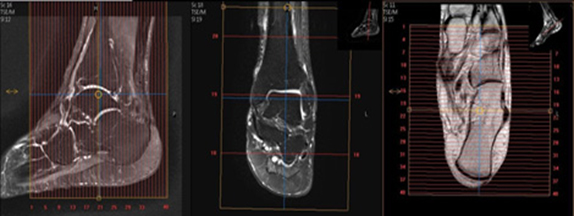

Angle to Tib/Fib (Ankle Protocol)

| AXIAL | T1 | TSE | 3mm | 0.3mm | None | 15cm | Cover thru Metatarsal Bases (as below) |

| AXIAL | T2 SPAIR | TSE | 3mm | 0.3mm | SPAIR | 15cm | Cover through metatarsal bases |

| SAG | T2 STIR | TSE | 3mm | 0.3mm | STIR | 15cm | Angle to Calcaneus |

| SAG | T1 | TSE | 3mm | 0.3mm | None | 15cm | Angle to Calcaneus |

| COR | T1 | TSE | 3mm | 0.3mm | None | 15cm | Perpendicular to Axial |

| COR | T2 SPAIR (run as STIR for infection) | TSE | 3mm | 0.3mm | SPAIR (or STIR) | 15cm | Perpendicular to Axial |